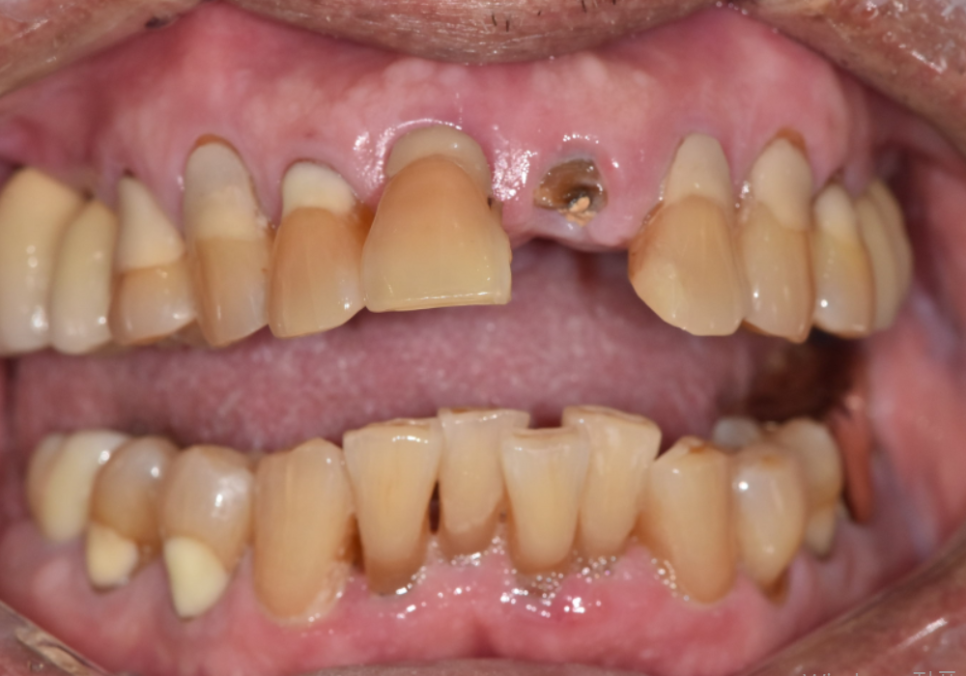

이 환자분은

왼쪽 앞니가 충치로 인해 부러지면서

내원하셨습니다.

겉으로 보면

앞니 하나만 문제가 있어 보일 수 있지만,

입안을 자세히 살펴보니

앞니 4개 모두 흔들림이 있었고

잇몸뼈 높이도 많이 낮아져

있는 상태였습니다.

250221

이런 경우에는

눈에 보이는 치아 하나만 보고 결정하면

오히려 치료가 더 길어질 수 있습니다.

앞니 임플란트 기간은

겉으로 보이는 모습보다

안쪽 잇몸뼈 높이나

염증이 있는지가

더 크게 영향을 주는 경우가 많기 때문입니다.